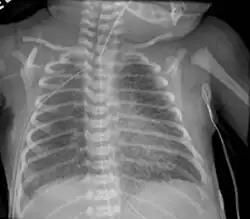

Pulmonary interstitial emphysema

Pulmonary interstitial emphysema is the condition of air escaping overdistended alveoli into the pulmonary interstitium. It is a rare disease that occurs most often in premature infants, even though it is possible to appear in adults.[26] It often presents as a slow deterioration with the need for increased ventilatory support. Chest x-ray is the standard for diagnosis where it is seen as linear or cystic translucencies extending to the edges of the lungs.[9]